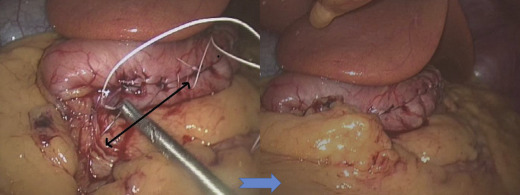

The surgical risk of LSG has decreased dramatically after the learning curve. Our series showed high incidence of leaks in the first 100 cases (9%) but low leakage rates in subsequent series due to improved surgical techniques. The formation of long and narrow gastric tubes will cause stricture if the gastric tube is sleeved too narrow at the incisura angularis angle. Usually endoscopic dilatation is effective at relieving the stricture but in difficult cases with long stricture, revision with roux-en Y gastric bypass is needed.29 Besides, laparoscopic seromyotomy of stricture areas has been used with good outcomes.30 Furthermore, we recognized that the slim gastric tube tend to coil medially once formed which would aggravate the severity of strictures, therefore it is essential to fix the gastric tube to the retroperitoneal tissue as an L-configuration tube (Fig. 2).

Fixation of gastric tube to retroperitoneum.

Figure 2.